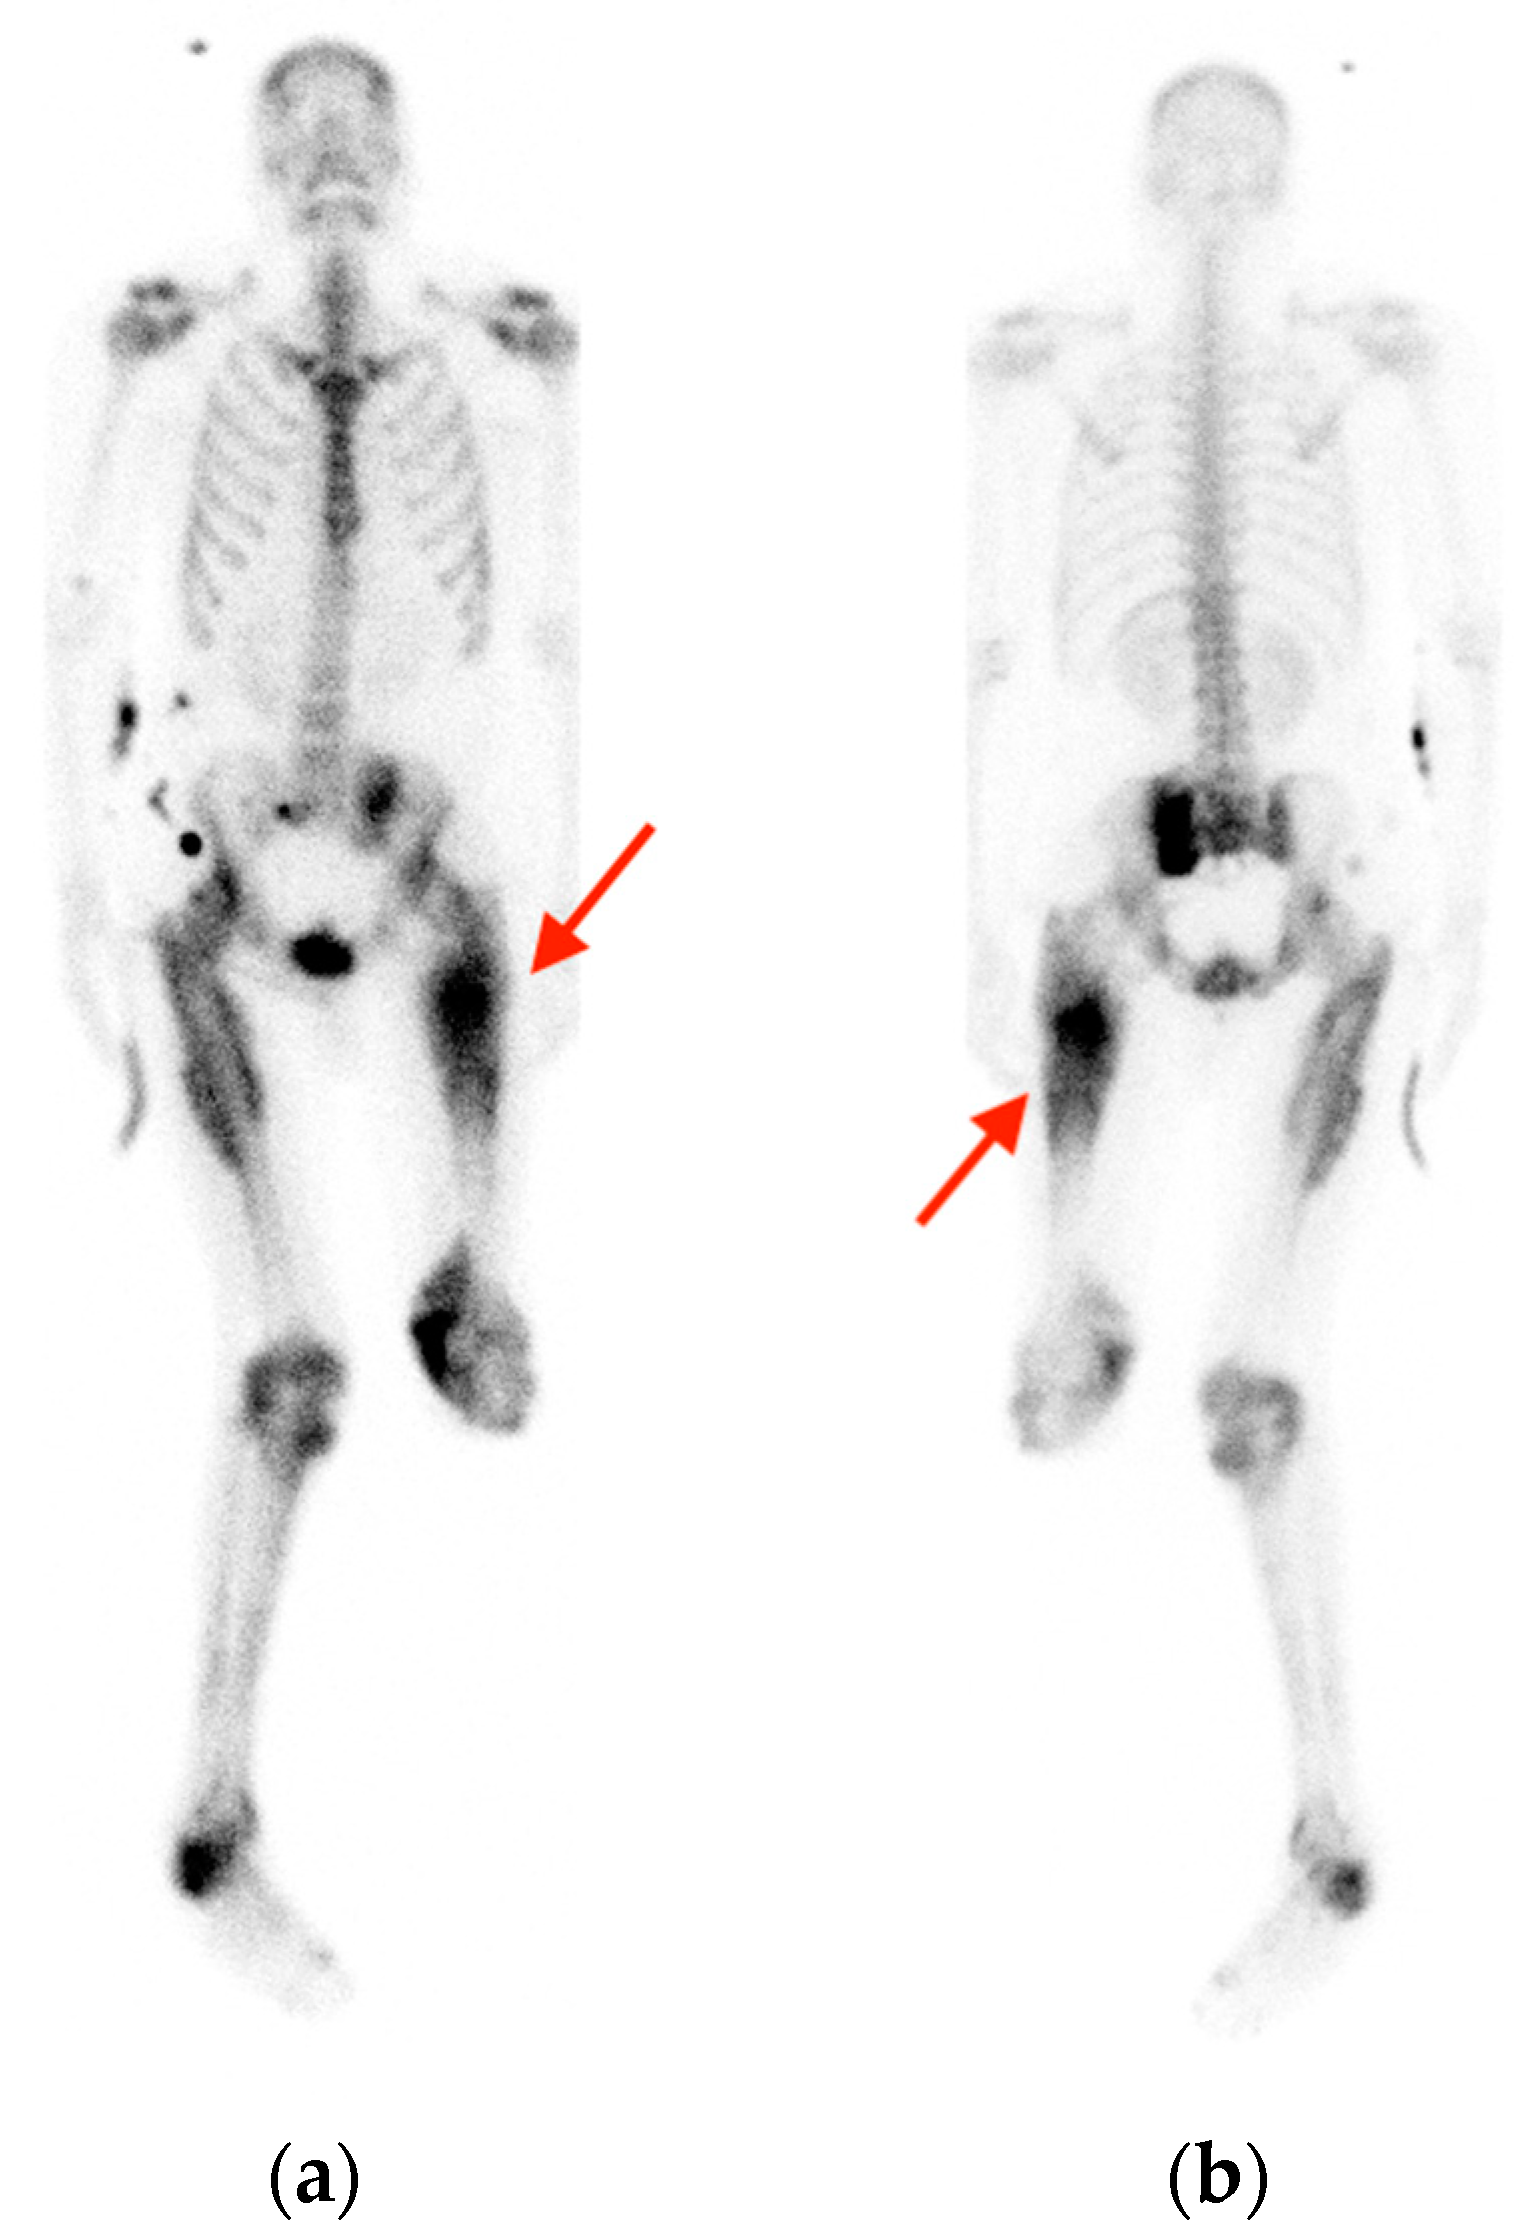

2.1. Fracture

- Oh, D.; Huh, S.J. Insufficiency fracture after radiation therapy. Radiat. Oncol. J. 2014, 32, 213–220. [Google Scholar] [CrossRef]

- Chung, Y.K.; Lee, Y.K.; Yoon, B.H.; Suh, D.H.; Koo, K.H. Pelvic Insufficiency Fractures in Cervical Cancer After Radiation Therapy: A Meta-Analysis and Review. In Vivo 2021, 35, 1109–1115. [Google Scholar] [CrossRef]

- Blomlie, V.; Rofstad, E.K.; Talle, K.; Sundfør, K.; Winderen, M.; Lien, H.H. Incidence of radiation-induced insufficiency fractures of the female pelvis: Evaluation with MR imaging. AJR Am. J. Roentgenol. 1996, 167, 1205–1210. [Google Scholar] [CrossRef]

- Abe, H.; Nakamura, M.; Takahashi, S.; Maruoka, S.; Ogawa, Y.; Sakamoto, K. Radiation-induced insufficiency fractures of the pelvis: Evaluation with 99mTc-methylene diphosphonate scintigraphy. AJR Am. J. Roentgenol. 1992, 158, 599–602. [Google Scholar] [CrossRef]

- Salavati, A.; Shah, V.; Wang, Z.J.; Yeh, B.M.; Costouros, N.G.; Coakley, F.V. F-18 FDG PET/CT findings in postradiation pelvic insufficiency fracture. Clin. Imaging 2011, 35, 139–142. [Google Scholar] [CrossRef]

- Zhong, X.; Zhang, L.; Dong, T.; Mai, H.; Lu, B.; Huang, L.; Li, J. Clinical and MRI features of sacral insufficiency fractures after radiotherapy in patients with cervical cancer. BMC Womens Health 2022, 22, 166. [Google Scholar] [CrossRef]